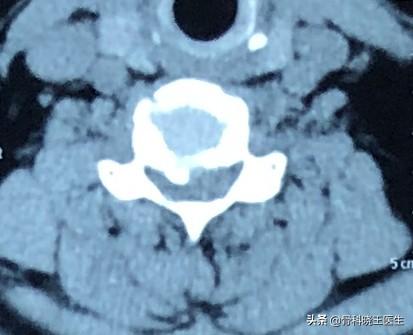

2.脊髄頚椎症:頚椎後縁の過形成、椎間板の後方ヘルニア、靭帯肥大、後縦靭帯の石灰化などが主な原因。手足の脱力や物を持つときのふらつきなどの症状を引き起こすこともある。

臨床の現場では、頸椎症患者や頸椎症患者には「脊椎性頸椎症」と呼ばれるカテゴリーがあり、一度診断された患者はすぐに手術しなければならず、保存療法を考慮する必要はない。

このタイプの頚椎症の発症率は15%前後で、予後が治療時期に左右されるため、臨床的障害率は極めて高い(大多数の患者はやみくもに手術を拒否し、手術を受けたがらないだけでなく、検査のために来院することすら嫌がるため、誤った治療法を採用しやすく、治療時期が遅れやすい)。